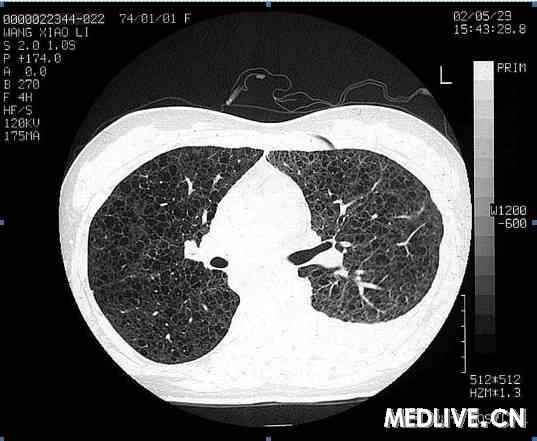

胸部高分辨CT(HRCT):双肺纹增多,紊乱,双肺弥漫性薄壁囊泡样改变(见图1)。超声心动图:少量心包积液, 腹部B超:肝、胆、胰、脾、双肾均未见异常。核素淋巴显像:考虑左侧乳糜胸为胸导管上段有瘘道进入胸腔。肺功能:一秒钟用力呼气量占预计值百分数( FEV1%pred )42.3%;最大肺活量占预计值百分数(FVC% pred)69.5%;一秒量占最大肺活量百分数(FEV1/FVC)53.0%;残气容积占预计值百分数(RV%pred)166%;肺总量占预计值百分数(TCL%pred)94.6%; 残气量占肺总量百分数(RV/TLC%)173%。气道可逆试验改善11.8%,一氧化碳弥散量(DLCO) 20.6%。提示:混合性通气功能障碍,弥散功能障碍。

图1 胸部高分辨CT(HRCT)显示双肺弥漫性薄壁囊状改变及左侧胸腔积液

LAM是乳糜胸的一个罕见原因。在北京协和医院,除特发性乳糜胸外,乳糜胸的主要原因为创伤性及结核(见表1),其他原因如淋巴瘤及丝虫病等也要注意。本例在鉴别诊断时需要仔细考虑这些疾病的可能。但由于同时合并双肺弥漫性囊状病变及气胸史,诊断的天平明显地指向罕见疾病LAM。双肺弥漫性囊性病变也需要与一些疾病相别,如肺气肿、肺间质纤维化(蜂窝肺)、囊性支气管扩张、组织细胞增生症X,及肺囊性纤维化等。根据病史及临床特点,鉴别起来并不难。HRCT在区分这些病变的特点时有突出的优势,对于了解病变类型,分布及特征很有帮助。

朱元珏教授(呼吸科):LAM较为罕见,但其临床表现如咯血、气胸、乳糜胸和呼吸困难在日常工作中经常碰到。LAM的HRCT有特征性改变,相信大家看过本例之后印象深刻。希望呼吸科医师一定要养成习惯,自己读片,而不仅仅是看放射科出的报告。LAM的囊状改变与小气道平滑肌增生后阻塞气道导致远端扩张有关,没有明显的肺间质改变。文献报道,LAM在肺移植后供体肺还可出现LAM的表现,因此,在其发病机制完全揭示之前,临床上的治疗较为困难。

本次再次推出一个罕见病是希望大家能从其诊治过程得到启发。本病表现为常见病,却是罕见病。病人在入院前经过一系列的检查和治疗,并按结核性胸膜炎治疗。在入院后,病房主管医师虽然没有诊断LAM的经验,但很快做出了正确的判断并经病理证实。其中有两点需要注意:⑴平时的鉴别诊断面要广,如本例是一个典型的LAM病例:育龄期女性/气胸/乳糜胸/双肺囊性改变,其诊断已经呼之欲出。LAM虽然罕见,大家没有什么经验,但由于平时在鉴别诊断中经常提起它,因此在理论上对它并不陌生,所以获得了迅速诊断。⑵HRCT的价值。由于本例在普通CT上不易觉察到典型的薄壁囊泡样改变,而在HRCT下却十分明显。对于任何怀疑肺气肿/肺大疱的病变,HRCT应更有优势,而且本例的肺功能提示残气量增加,在选择CT时应申请HRCT。对于这一病例的治疗,林教授也做了很好的讨论。由于目前的治疗方法并无确切依据,根据每个病人的基础状况选择治疗方案十分重要。而对于这样一个少见病,病人间以及病人和专业人士间的互相支持也很重要,因特网为此提供了很好的工具。